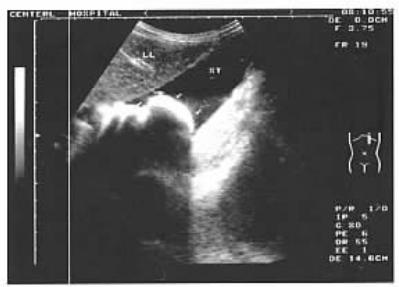

3.B超

可见到胃内有强回声团块影。

箭头所指为胃石[5]。4.CT

[5]梁君佐.胃石症1例的超声所见[J].中国超声医学杂志,2004,20(6):437.DOI:10.3969/j.issn.1002-0101.2004.06.025.